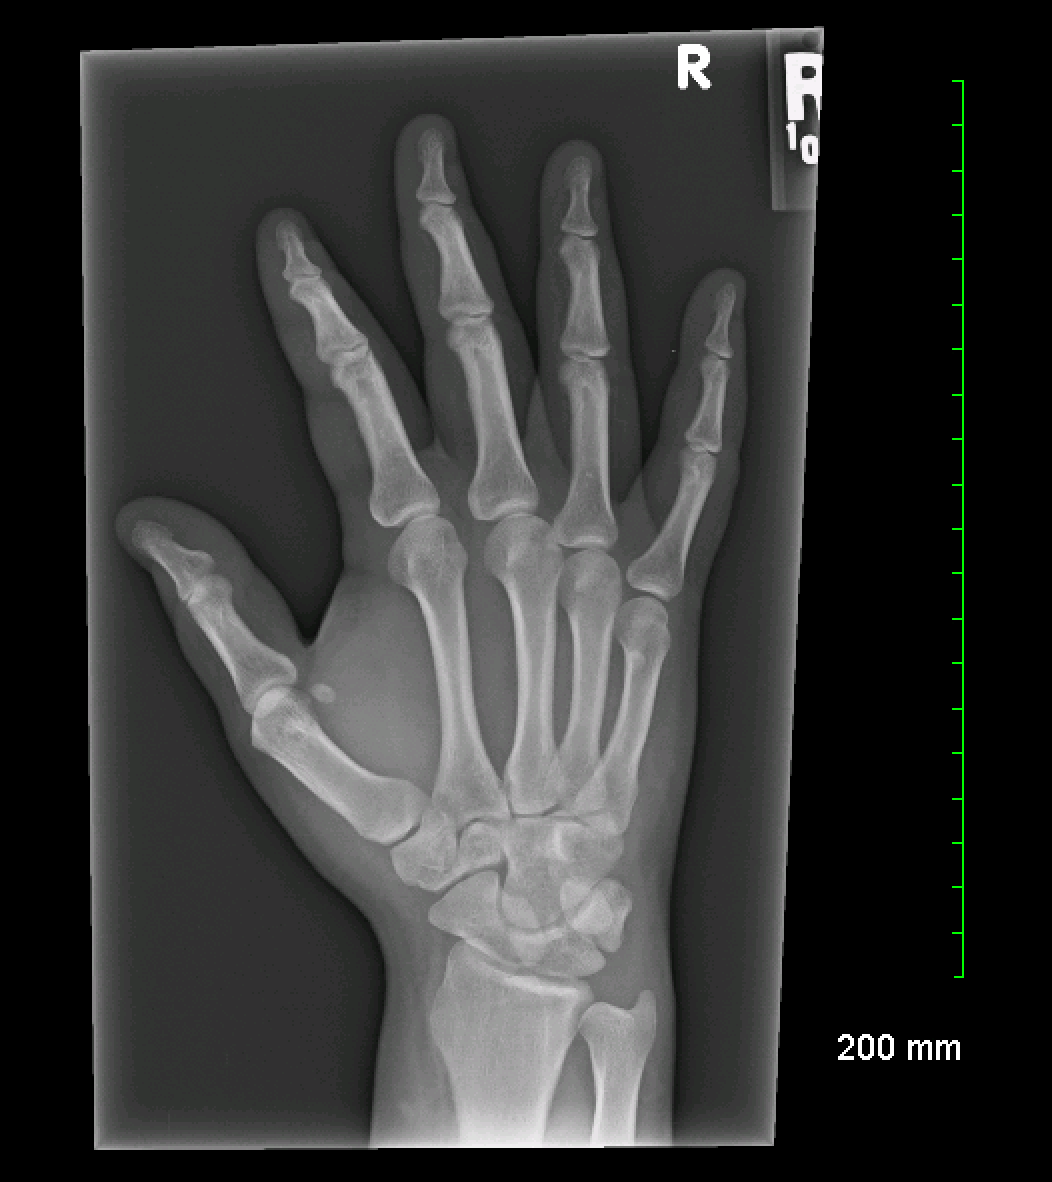

Prepare to be captivated by Top, a showcase of x ray of right hand and wrist imagery powered by wonderkidsmontessori.edu.vn. More related visuals are below.

x ray of right hand and wrist

Posts: x ray of right hand and wrist